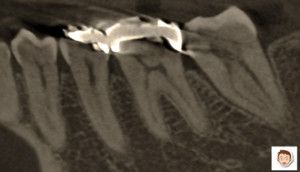

部分的なレントゲン

コラム「部分的なレントゲン」の画像